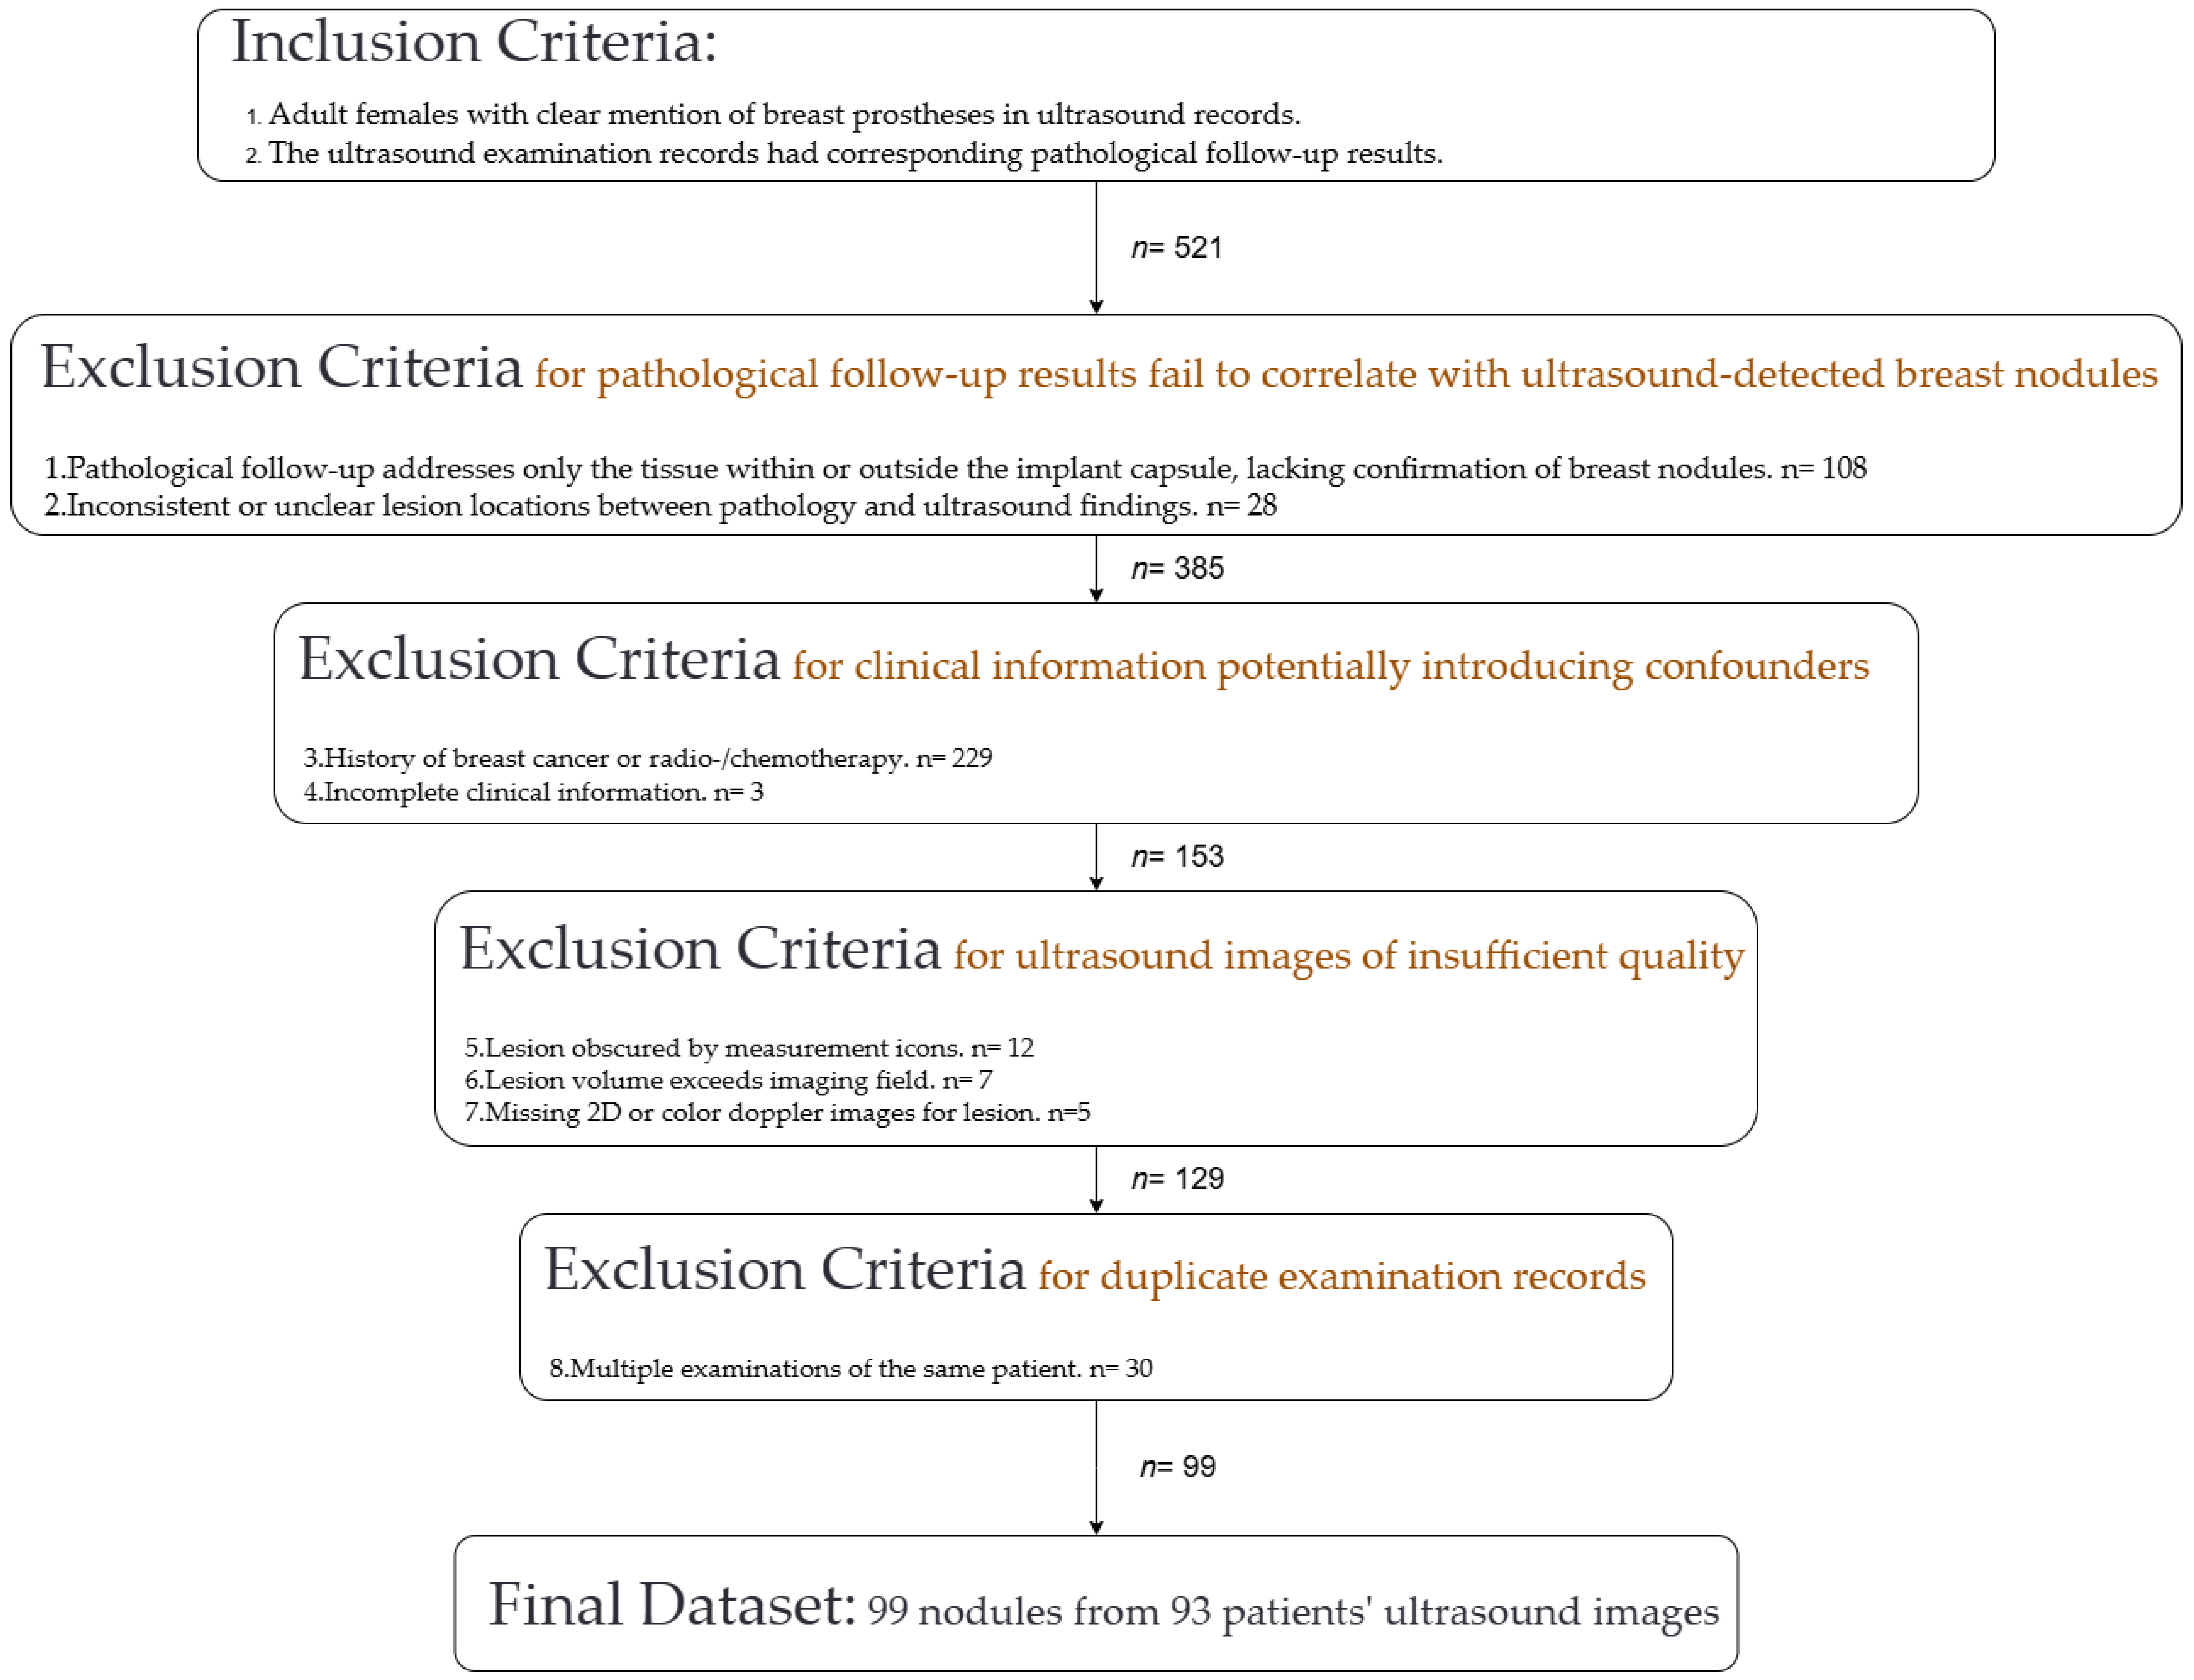

2.2. Study Subjects